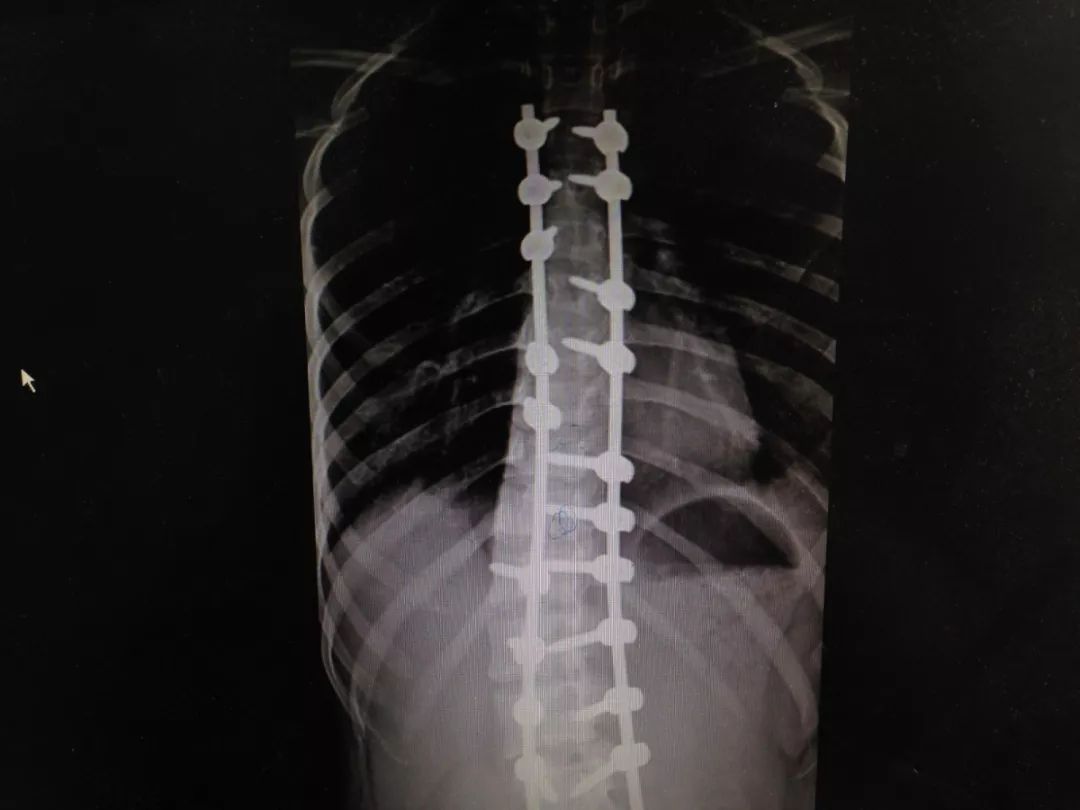

18岁脊柱侧弯术后